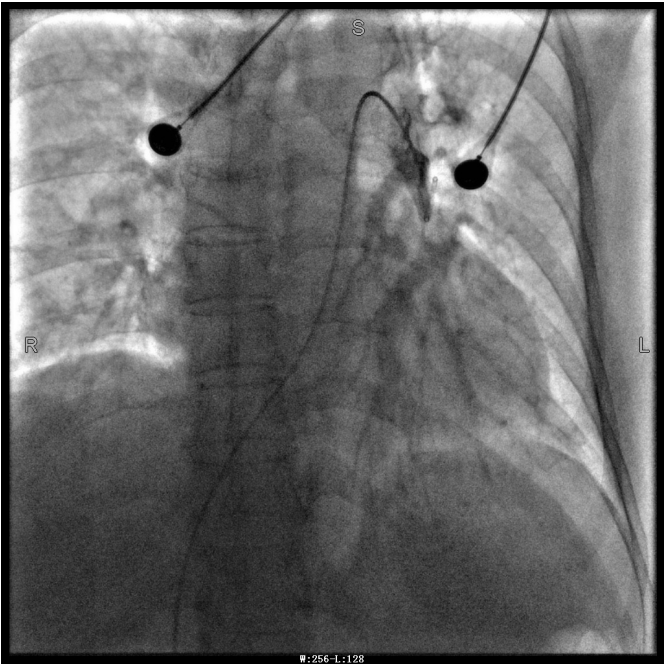

谭婆婆今年已经72岁了,因“突发意识障碍2次”到璧山区人民医院神经内科治疗。谭婆婆没有基础心脏病病史,但近段时间活动耐量明显下降,稍做活动就出现呼吸困难。入院后查BNP及心脏彩超均未提示明显异常,查D二聚体明显升高,经心血管内科周波医师会诊后转入科室继续治疗。在心血管内科主任、内科学(心血管病)博士于长青的指导下,周波医师成功完成医院首例“一站式”微创介入手术。在影像中,可以清晰地看到堵塞的血管经溶栓治疗后,重新畅通无阻,流动起支撑生命的血液。

第三章未标注图像为术后图像